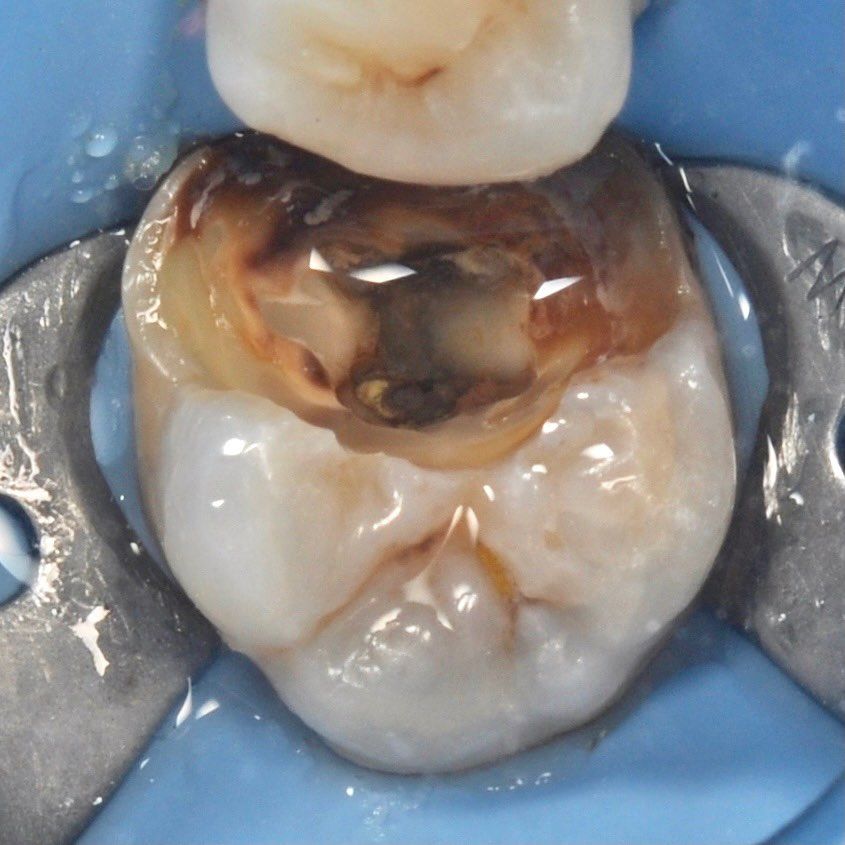

Root canal treatment

careful treatment of canals

Accurate determination of the geometry of the channels and their high-quality processing

caries removal